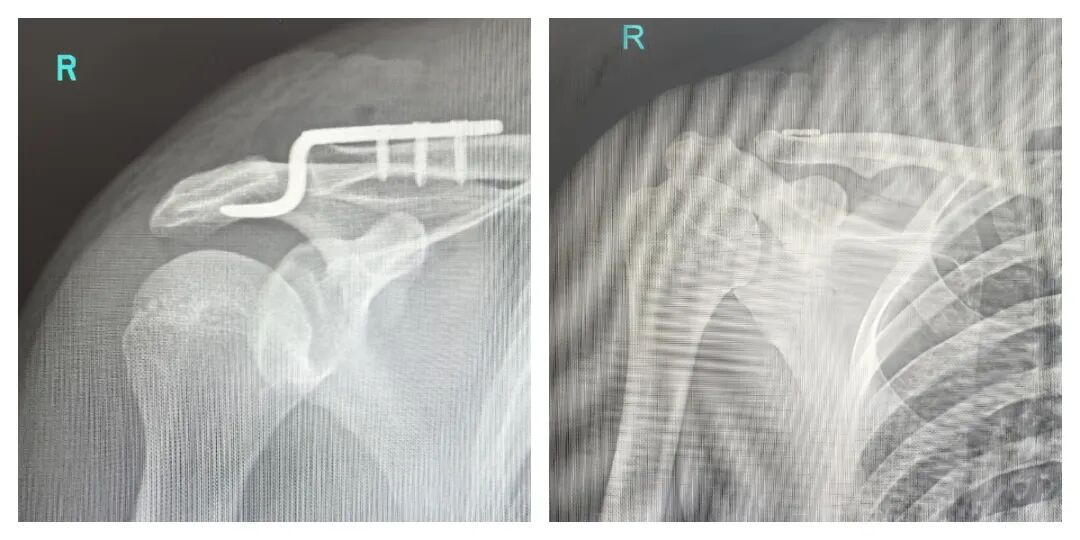

左为传统治疗影像图,右为患者微创治疗后影像图

“过去治疗肩锁关节脱位,切口需要‘大开大合’,如今只需几个钥匙孔大小的切口,就能精准复位。” 骨伤二科主任孙云明介绍,传统肩锁钩钢板手术需大面积切开组织,术后易遗留肩关节功能障碍,且患者需二次手术取出钢板。而关节镜下双袢固定术借助高清影像系统与精密器械,实现解剖复位与弹性固定,创伤小、恢复快,更免去了二次手术的经济与心理负担。